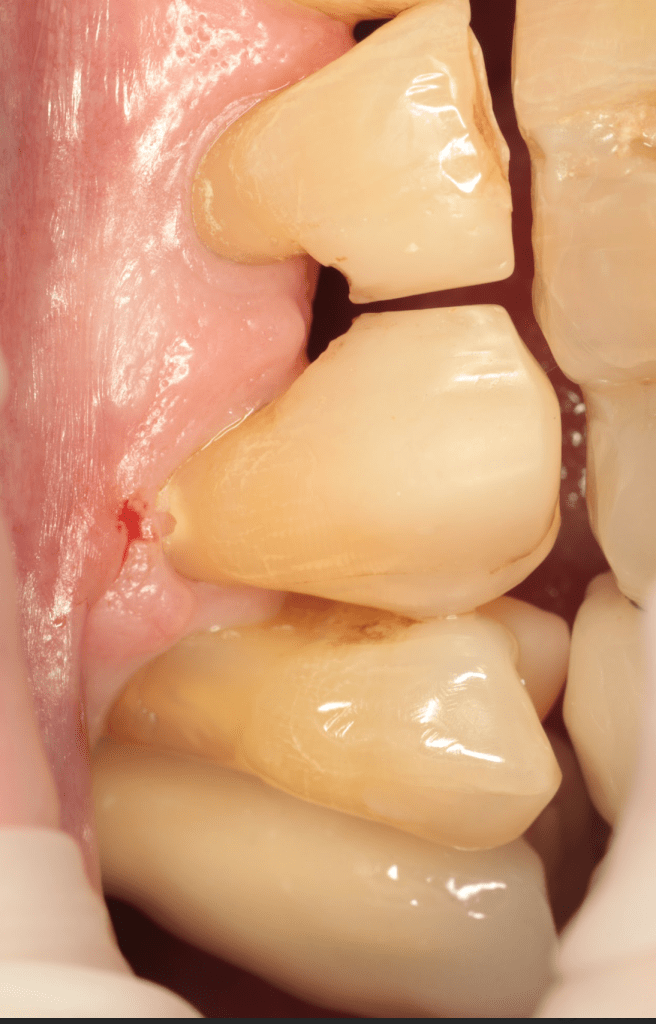

Reabsorción externa, tratamiento quirúrgico

Gingivectomía +reco preendo +reconstrucción

Reco pre-endo gingivectomái, pared yuxtaosea

Reco preendo + gingivectomía